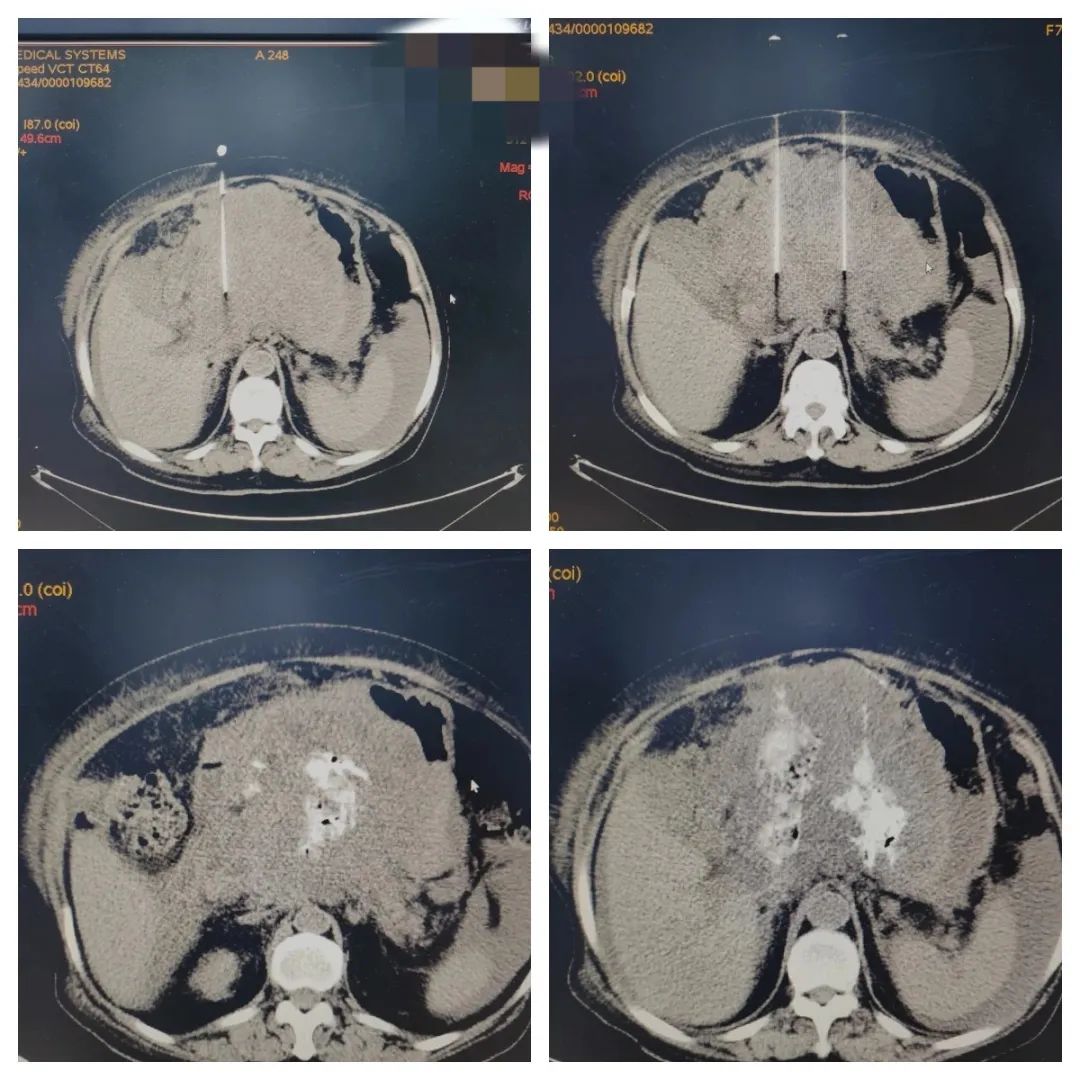

12月13日下午,吕行团队开始为黄阿姨进行无水乙醇瘤体内注射。操作前先给患者进行CT扫描,寻找最大和安全层面,确定穿刺点,测量安全穿刺深度。按CT测量提供深度、角度,将无水酒精注射针刺入预定位置和深度,经CT扫描确认后,将20ml无水乙醇分别抽入二个注射器并分别与造影剂混合形成混悬液,在穿刺点顺利完成注射。

CT扫描确认,无水乙醇和造影剂混悬液在瘤体内扩散充盈明显,治疗有效。随后将患者用轮椅送返病房,术后患者无明显不适。